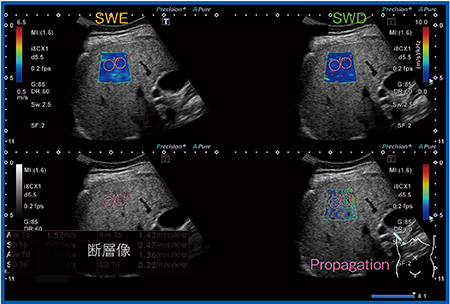

なお,Aplio iシリーズでは,SWE,Dispersion表示(SWD),Propagation表示に加え,バックグラウンドの断層像を4画面表示で同時に観察可能なほか(図1),集積したデータを数値で一覧表示することができ,非常に便利な機能となっている。

図1 Aplio iシリーズの4画面表示

(70歳代,女性,F3,NASH症例)